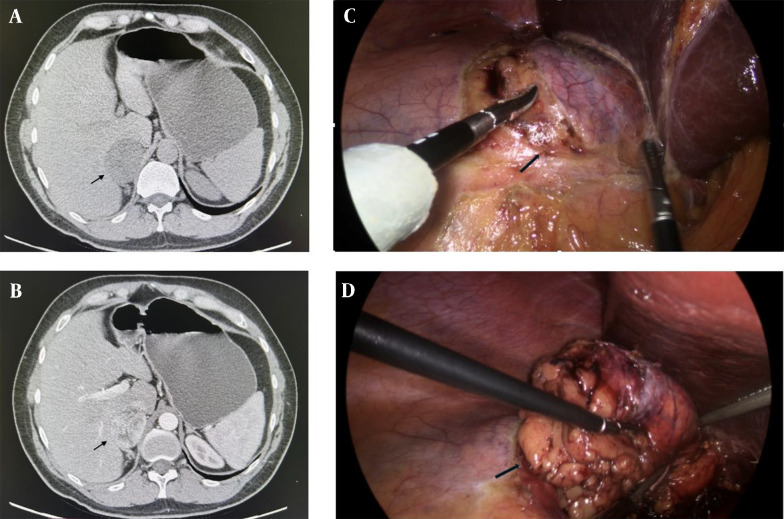

Case presentation: A 44-year-old male patient was admitted to the clinic for endocrine surgery for laparoscopic surgery of a right adrenal gland incidentaloma measuring 57 × 47 × 59 mm, discovered during a routine abdominal ultrasonography. The patient had a history of hypertension but no other comorbidities. Biochemical and physical examinations revealed no signs of hypercortisolism. Urinary metanephrine and normetanephrine levels were within normal limits. A right laparoscopic adrenalectomy was performed, and a 5 cm tumor was identified without evidence of locoregional invasion. Pathological examination confirmed a Sertoli cell tumor of the adrenal gland. Immunohistochemical analysis revealed positive staining for vimentin, steroidogenic factor 1 (SF1), and beta-catenin, while chromogranin A, hCG, PSA, and TTF1 were negative. The Ki-67 index was 3%. The patient was subsequently referred to a urologist, where testicular ultrasonography showed no abnormalities. There were no signs of recurrence during a 15-month follow-up period. Additionally, the patient's biannual antihypertensive treatment was discontinued by a cardiologist 1.5 months post-surgery.